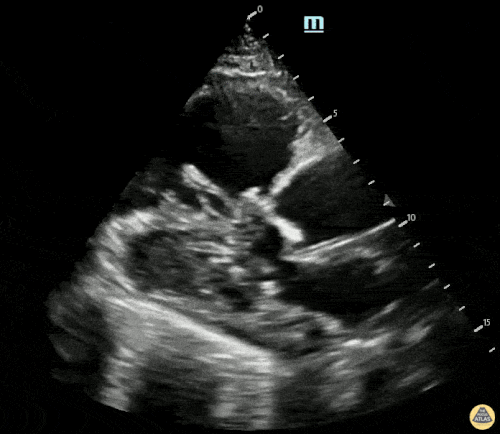

Sol ventrikül fonksiyonunun değerlendirilmesi

Sol ventrikül (LV) fonksiyonu dört pencerenin tamamında değerlendirilebilir; ancak genellikle parasternal uzun aks görüntüsünde en kolay şekilde incelenir. Değerlendirme iki şekilde yapılabilir:

Görsel (subjektif) tahmin

EPSS (End Point Septal Separation) ölçümü

Çok sayıda çalışma, acil hekimleri ile kardiyologlar arasında global kardiyak fonksiyonun görsel değerlendirilmesi açısından yeterli uyum olduğunu göstermiştir.

RUSH muayenesinde genellikle ejeksiyon fraksiyonunun tam yüzdesine odaklanmak yerine, sol ventrikül fonksiyonunu geniş kategoriler halinde sınıflandırırız:

Hiperkinetik (hiperdinamik)

Normal

Azalmış (düşük)

Azalmış sol ventrikül fonksiyonunu düşündüren hızlı ve pratik bulgular şunlardır:

Sol ventrikül kavite çapının sistolde yaklaşık üçte bir oranında küçülmemesi

Miyokardın sistol sırasında yeterince kalınlaşmaması

Mitral kapağın ön yaprağının diyastolde septuma yaklaşmaması

Buna karşılık hiperdinamik bir kalpte, sistolün zirvesinde ventrikül duvarlarının neredeyse tamamen kollabe olup birbirine temas ettiği izlenir.